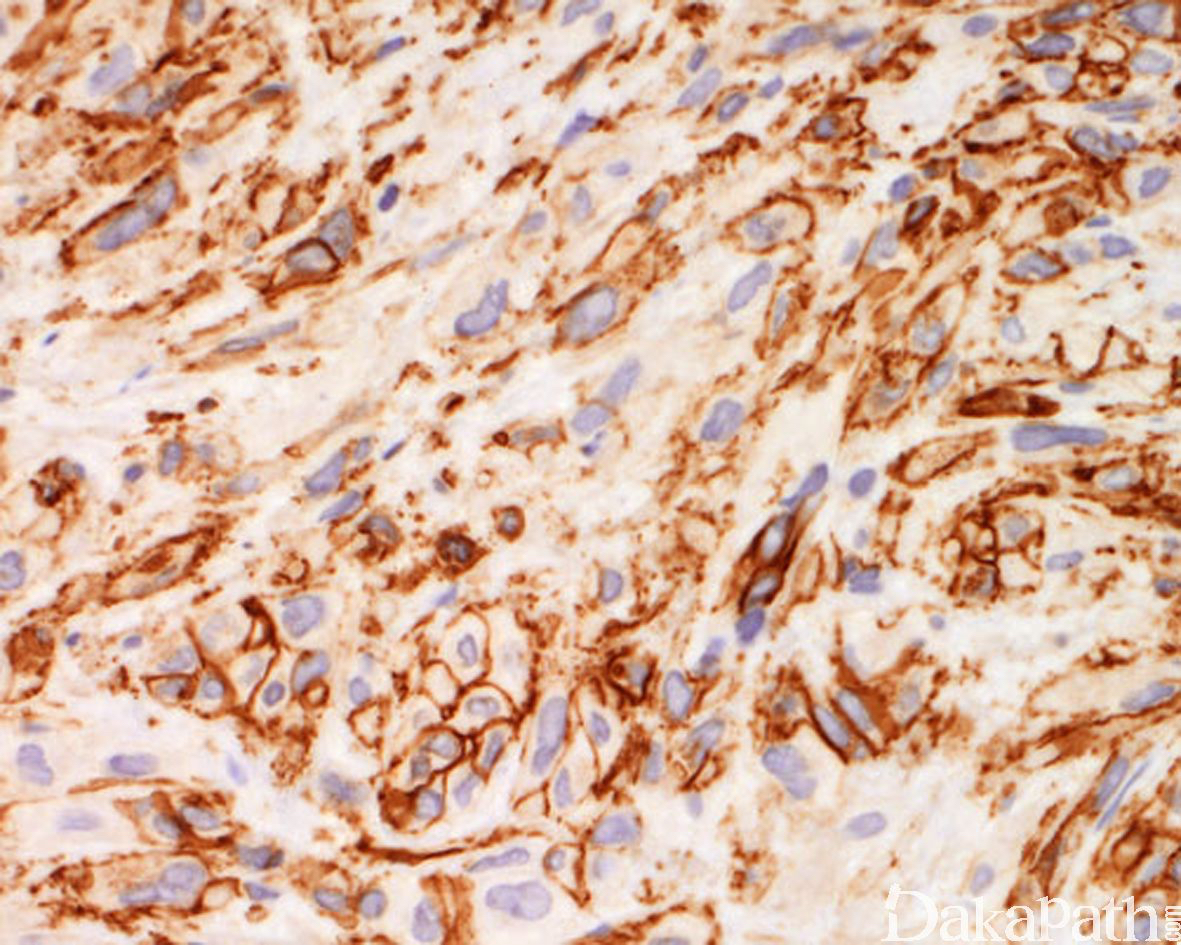

免疫组织化学染色:

肿瘤细胞恒定表达 FOSB、AE1/AE3. ERG、FLI-1. INI1,CD31 表达不一,较少表达 EMA,部分表达 SMA,而 CD34. Desmin、MyoD1. S100 阴性,INI-1 无表达缺失